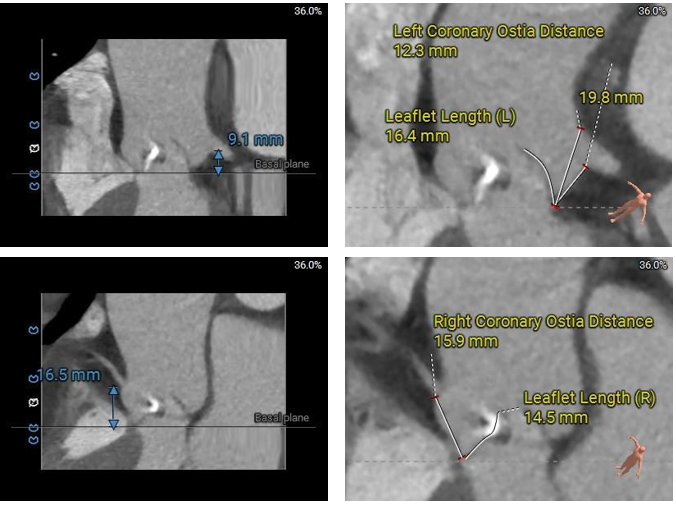

Type 0型二叶瓣,小瓣环,流出道偏小,轻度钙化,钙化主要分布在大弯侧瓣叶边缘,瓣上限制轻

左冠开口低,左侧瓣叶偏长,窦部空间可,冠脉遮挡风险不高

入路血管走形良好,零星附壁钙化,内径可,整体入路血管条件良好